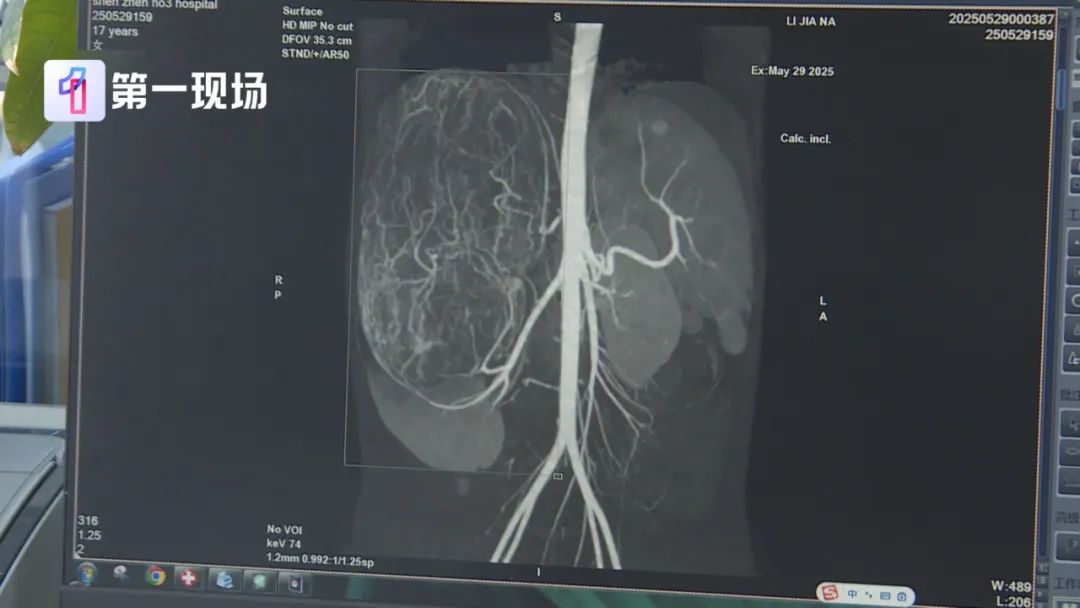

等到了当地医院一检查,CT结果显示,她的右肾有恶性肿瘤伴肝转移可能,家长就立即带着孩子来到深圳求医。

深圳市第三人民医院肾移植二科主任胡红星介绍,肿瘤切出来后,经测量大小有27厘米,重量有2.435公斤,非常大。